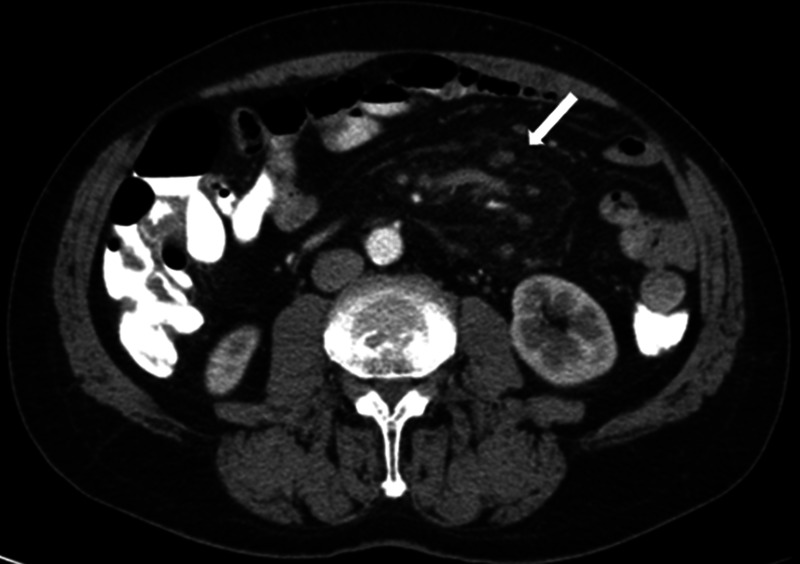

Figure 2.

Axial contrast-enhanced CT image showing a hyperattenuated fatty mass with pseudocapsule (arrow) at the mesenteric root.

Figure 3.

On axial contrast-enhanced CT image, multiple mesenteric lymph nodes and preservation of fat around vessels and lymph nodes (fat ring sign, arrow) are seen in the hyperattenuated fatty mass.